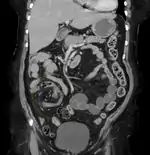

Coronal CT of the abdomen, demonstrating a volvulus as indicated by twisting of the bowel stock